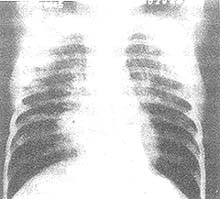

普通問質性肺炎

普通問質性肺炎,又叫間質性肺疾病、瀰漫性肺疾病等,作為病名,只有十多年的歷史,顧名思義它是肺間質的病變。間質性肺炎不是一個單一的疾病,而是一大類疾病的總稱,約有百餘種。

普通問質性肺炎,又叫間質性肺疾病、瀰漫性肺疾病等,作為病名,只有十多年的歷史,顧名思義它是間質的病變。間質性肺炎不是一個單一的疾病,而是一大類疾病的總稱,約有百餘種,已知一小部分病因已明,如塵肺、藥物性肺炎放射性肺炎等;但有相當一部分病因不明,如特發性肺纖維化、結節病等。間質性肺炎雖然稱為“肺炎”,但主要不是由細菌、病毒等微生物感染而成